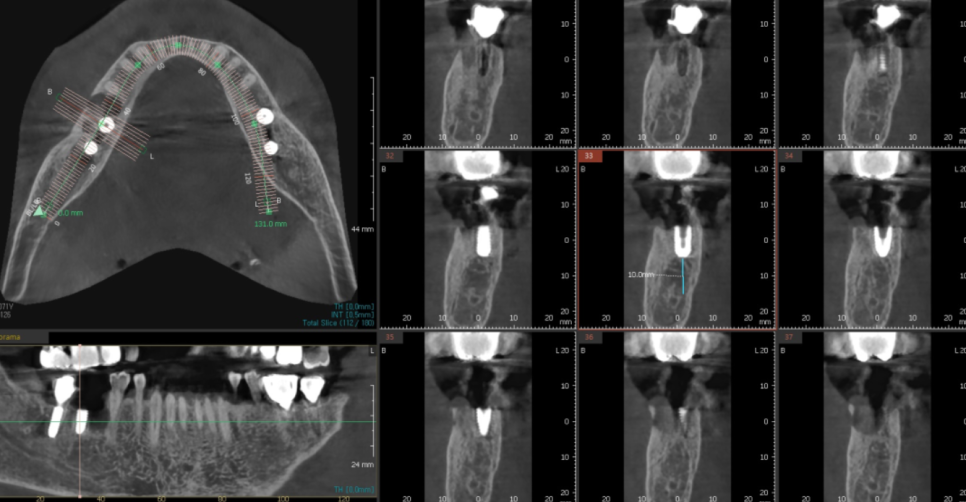

ct에서 분석 했을 때

뼈가 좀 모자란 부분이 있어서

뼈이식도 함께 시행했는데요.

잇몸뼈가 부분적으로 녹은 부분이 있었습니다.

잇몸 앞쪽으로 뼈가 없다보니

임플란트 위치를 뼈가 많은 뒤쪽으로 심어드렸습니다.